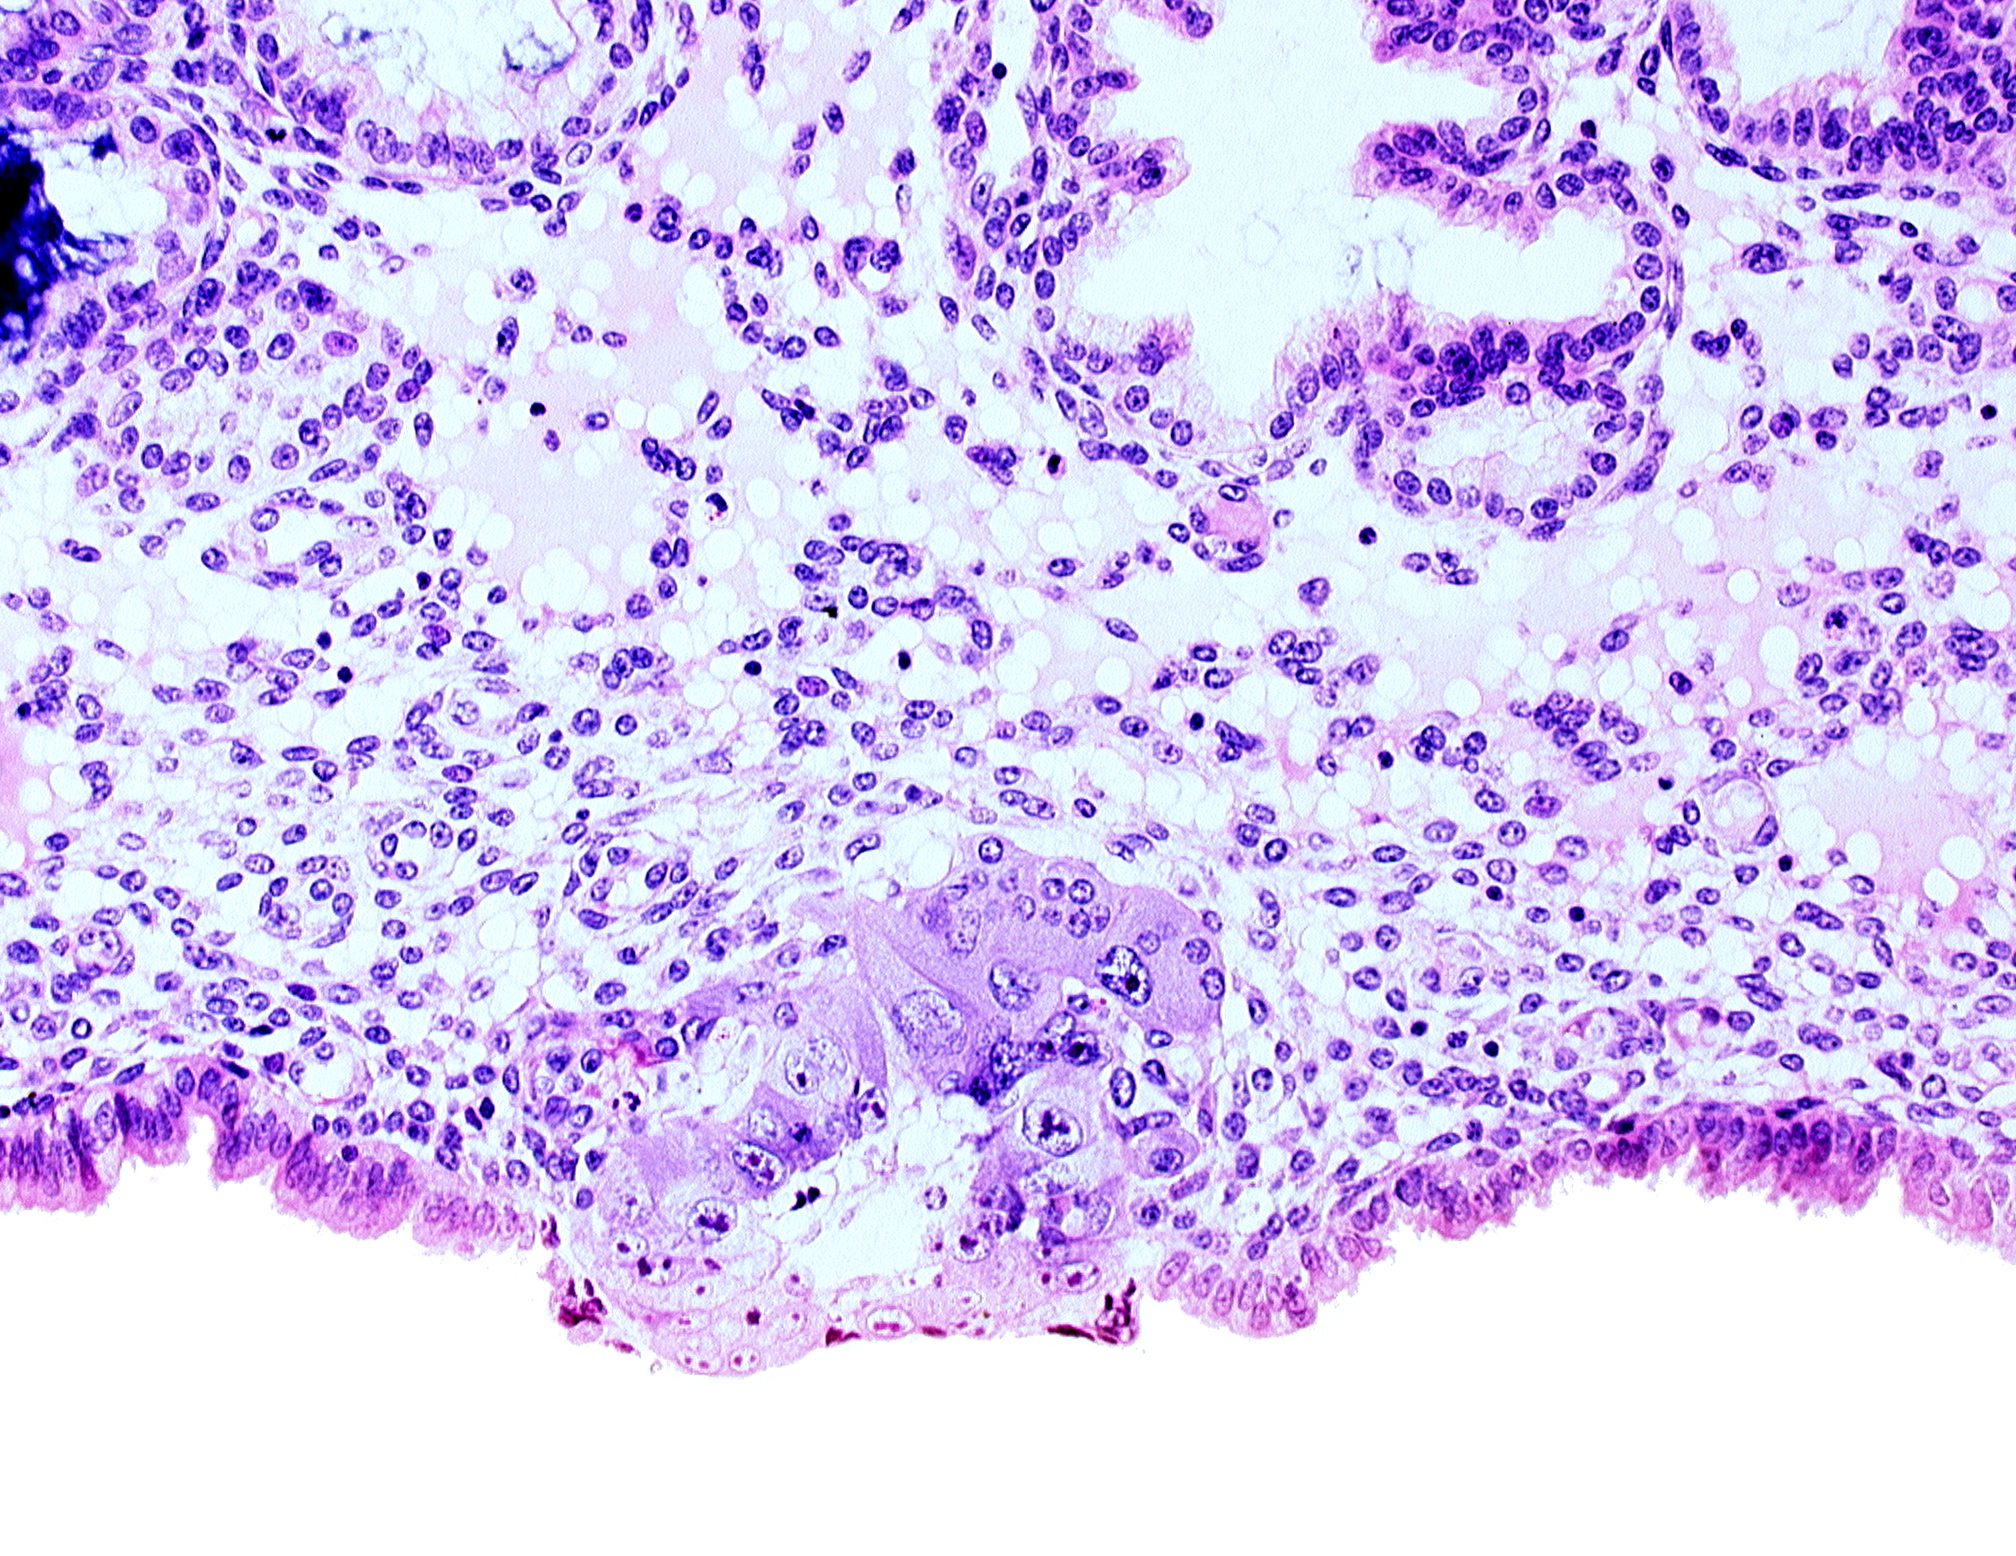

Carnegie Embryo #8155 | Location: 04-03-08

Keywords: blastocystic cavity (blastocoele), cytotrophoblast, solid syncytiotrophoblast